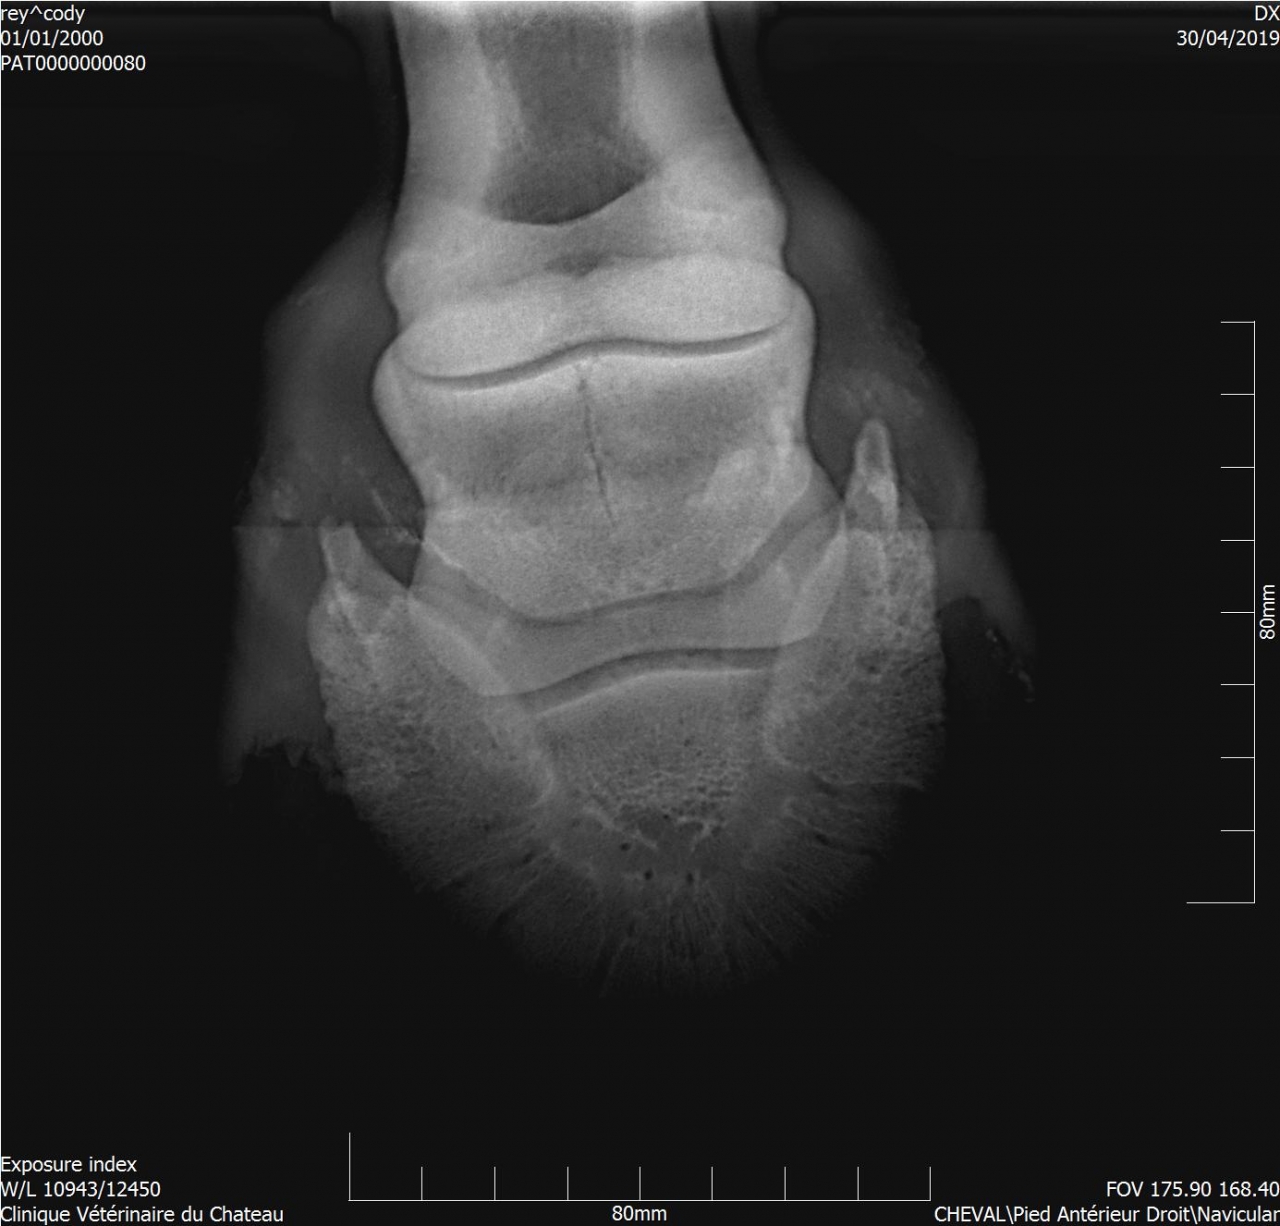

| Dire merci | Les radios ont été faites hier, il y a clairement un souci sur le naviculaire antérieur droit (le véto m'a montré le cliché sur l'écran). |

| Dire merci | Dès que j'ai les radios je ferai le point avec le véto. Il a effectivement parlé d'un tendon qui viendrait frotter sur l'os et sur la nécessité d'adapter le parage. La boiterie est très légère, et ne permet pas de faire le test en anesthésiant une partie du pied. |

| Dire merci | Je mettrai les radios dès que je les aurai. Je ne sais pas dans quel état est l'os naviculaire. Le principal c'est d'apporter du confort à Cody. Pour le moment il est sous anti inflammatoires pendant une semaine. Je vais sans doute tester un complément alimentaire le Nav X Gold de chez Hilton Herbs. Le véto a conseillé de l'Osteosin. |

| Dire merci | Voici le compte-rendu du véto : Examen général: L’examen locomoteur au pas et au trot en ligne droite ne met pas en évidence de boiterie. Le cheval pose l’antérieur droit en deux temps : pose d’abord en muraille externe puis en interne. Une boiterie 2/5 de l’antérieur gauche apparait sur le cercle au trot à droite Examens complémentaires : Radiographie : Pieds de face : 3-4 fossettes synoviales sur le bord distal du naviculaire antérieur droit, de profondeur faibles et peu ouvertes. 2-3 fossettes synoviales dont l’une plus ouverte sur le bord distal du naviculaire antérieur gauche Léger pincement articulaire p1-p2 et p2-p3 coté externe visible sur le membre à l’appui. Boulet de face : Petit remaniement osseux au niveau de l’insertion proximale du ligt coll int Boulet et pieds ant droit de profil : ras La boiterie étant trop légère pour préciser la localisation par anesthésie étagée, plusieurs hypothèses sont envisagées. Par ordre d’importance : • Pincement et fatigue articulaire lié au parage ou à une compensation d’une légère entorse boulet • Entorse du boulet • Début syndrome podotrochléaire Message édité le 14/05/19 à 18:37 |